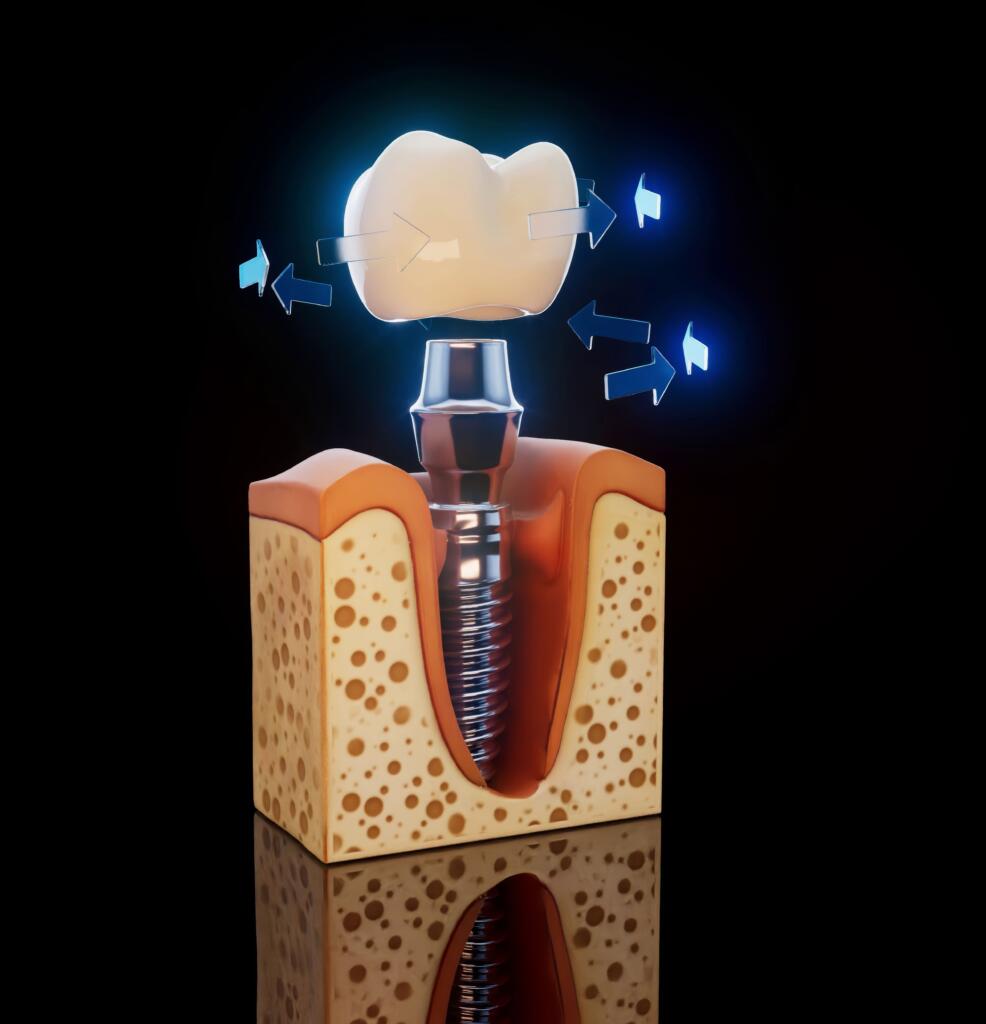

İmplant eksik dişlerin tedavisinde kullanılan ve çene kemiğinin içine yerleştirilen titanyumdan yapılmış vidalardır. Bu vidaların üzerine diş protezi yerleştirilir. İmplant tedavisinin diğer tedavilere avantajı komşu dişlere zarar verilmez. Yani komşu dişlerin kesilmesi gerekmez. İmplant diş kök görevi görür ve doğal diş gibi rahatlıkla yemek yiyebilir, konuşabilir ve gülebilirsiniz.

İmplant tedavisi hastaya hafif bir lokal anestezi verilerek yapılır. İşlemden önce detaylı muayene ve röntgen gereklidir. Çene kemiklerinin ve kalan dişlerin ölçüsü alınır. Dental implantların yerleştirilmesi için iki seçenek vardır. Tek aşamalı işlemde implant yerleştirildikten sonra geçici başlık takılır. İki aşamalı işlemde ise dental implant takıldıktan sonra üzeri diş eti ile kapatılır ve iyileşmeye bırakılır. Protez başlıklar daha sonra takılır. Her iki durumda da geçici bir köprü yerleştirilir ve alt çene için 3 ay, üst çene için altı ay iyileşme süreci beklenir. Bazen dental implantların üzerine yeni yapılan dişler hemen takılabilir. Dental implantla hasta güvenle gülebilir ve yemek yiyebilir.

Zirkonyum implantlar, titanyumdan yapılmış implantların direncini artırmak için yapılmış yeni kuşak implantlardır. Özellikle dar çene kemiğinde dayanıklılığı artırmak için kullanılır. Titanyumdan dayanıklılık haricinde farkı yoktur.